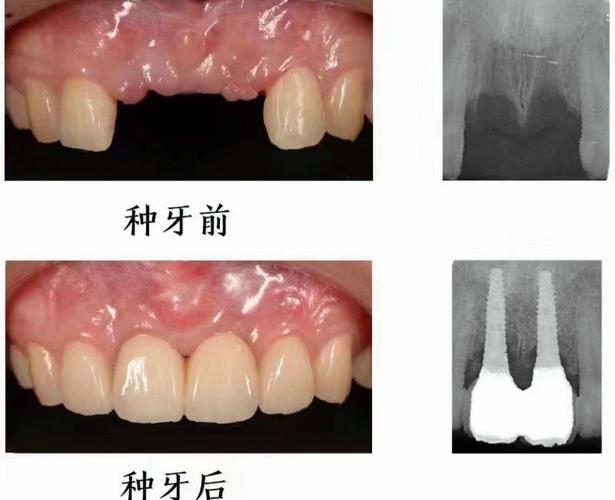

(图片来源网络,侵删)- 价格范围广: 种植牙费用受多种因素影响:种植体品牌(如瑞士Straumann、瑞典Nobel Biocare、德国Ankylos、韩国Osstem/Dentium等)、牙冠材料(全瓷、烤瓷)、是否需要植骨、上颌窦提升、是否使用数字化导板、医院等级、医生资历、诊所定位等,在广州,单颗种植牙的总费用(含种植体、基台、牙冠)从几千元到两三万元甚至更高都有可能。

- 种植体品牌与选择: 了解医生推荐使用的种植体品牌、型号、产地、特点、质保政策(种植体本身通常有5-10年质保,但具体看品牌和诊所政策),不同品牌在初期稳定性、长期成功率、生物相容性等方面有差异,价格也相差较大,了解医生为什么推荐这个品牌。